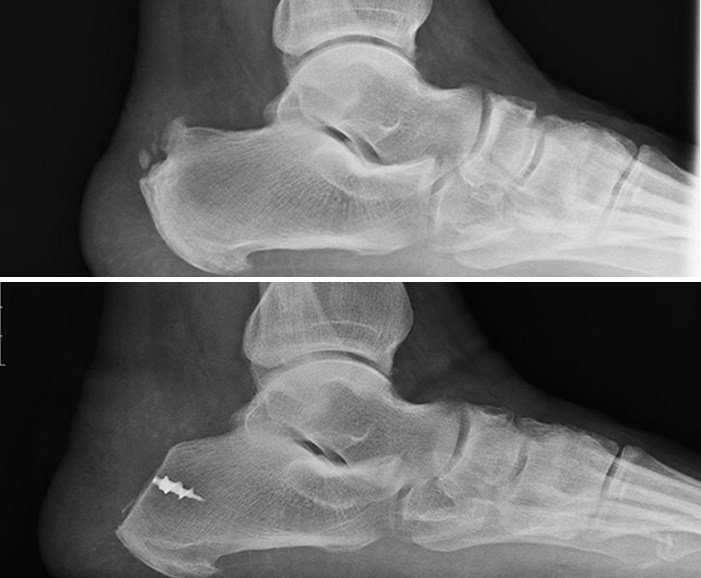

The diagnosis is usually obvious. There will be visible swelling and redness on the back of the heel and the patient will be tender at the attachment site of the Achilles tendon where the bone spur is palpable. X-rays will confirm the presence of a bone spur on the back of the heel. MRIs can be useful to determine the extent of damage to the Achilles tendon.

If conservative treatment fails, surgery involves removal of the bone spur from the back of the heel. To do this the Achilles tendon may have to be partially detached from the heel and then repaired back to the bone. After a period of immobilization and non-weight bearing, the patient will need to go to physical therapy. It can take several months for the heel to feel better after this surgery because the Achilles tendon has a very poor blood supply.